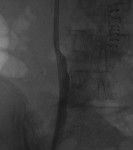

Access was gained from the back into a dilated posterior calyx of each kidney and secured with a sheath. Antegrade pyelogram on each side revealed marked ureteral and calyceal dilation due to complete obstruction of the distal ureter. A wire was advanced into the urinary bladder past the obstruction, which was dilated with a non-compliant balloon when it resisted the deployment of a nephroureteral stent. The stent was successfully deployed after the balloon dilation.

If obstructions are easy to cross, internal ureteral stents may be placed across them, with one end of the stent in the renal pelvis and the other in the urinary bladder. The stents should be changed periodically through the urethra by urologists or interventional radiologists. Sometimes, as in the patient whose images are displayed above, the obstruction must be predilated to permit insertion of the ureteral stents. Alternatively, a drainage catheter called a nephrostomy catheter can be deployed into the renal pelvis to drain urine into a bag attached to it without crossing the obstruction.

Internal ureteral stents are preferable over nephroureteral stents, which are also placed by interventional radiologists but differ from ureteral stents in having their proximal segments outside the patient, so that urine not only drains down their internal segment into the urinary bladder, but is also diverted into a bag attached to the hub of their external proximal end. They differ from nephrostomy catheters in having an internal component continuous with their external component and that runs down the ureter to the urinary bladder.